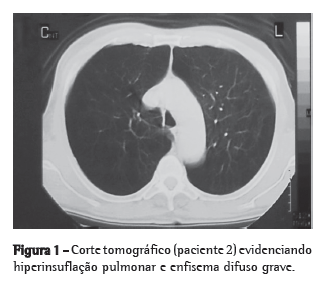

A bleomicina ou a salina foram administradas 3 dias após o início do tratamento com quercetina ou veículo (Figura 1). Os tratamentos continuaram por mais 14 dias após a injeção intratraqueal, e então os hamsters foram sacrificados.